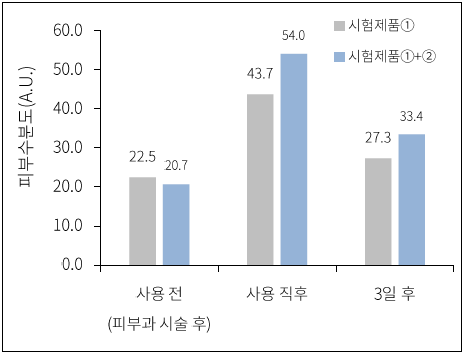

*Hiệu quả thực tế có thể khác nhau do thử nghiệm nội bộ. Đánh giá hiệu quả dưỡng ẩm sau 3 ngày sử dụng sản phẩm, ngày 18-21 tháng 4 năm 2022, Cosmax

Kết quả thực nghiệm

Sau khi tác động kích thích bên ngoài vào cả hai bên má của đối tượng,

chất thử nghiệm (PixelBiome™) được bôi lên một vùng

để kiểm tra mức độ làm dịu vùng da bị kích ứng.

PIXCELL BIOM™ Xác minh lần 3

Đã hoàn thành các thử nghiệm lâm sàng chính thức với các kích thích bên ngoài cực độ

Sau khi tác động các kích thích bên ngoài nhân tạo vào cả hai bên má của đối tượng, chất thử nghiệm (PixelBiome™) được bôi

lên một vùng để kiểm tra mức độ làm dịu vùng da bị kích ứng.

Kết quả thực nghiệm

Trong nhóm đối chứng thử nghiệm sử dụng dung dịch gốc PixelBiome™, các tác động đáng kể đã được xác nhận về kết cấu da (độ nhám), độ bóng, độ trong suốt, màu sắc và

độ ẩm sau khi kích thích bên ngoài .

(Cơ quan nghiên cứu: Trung tâm nghiên cứu lâm sàng về da KSRC Hàn Quốc & Bệnh viện Bundang, Đại học Quốc gia Seoul, Khoa Phẫu thuật thẩm mỹ / 15 tháng 2 năm 2022 – 21 tháng 4 năm 2022 / 21 đối tượng)

*Đánh giá tác dụng của ‘Dung dịch PixelBiome™ Original 2 tỷ/mL’ trong việc cải thiện mật độ da người / 4 tháng 1, 2022 – 3 tháng 2, 2022 / 20 phụ nữ (30-55 tuổi) / Trung tâm nghiên cứu lâm sàng về da KSRC Hàn Quốc

*Đánh giá hiệu quả cải thiện làn da của con người bằng ‘dung dịch PixelBiome™ nguyên bản 2 tỷ/mL’ sau khi kích thích tạm thời bằng Fraxin** Re** / 22.02.15~22.04.21 / 21 phụ nữ từ 20~43 tuổi / Trung tâm nghiên cứu lâm sàng về da KSRC Hàn Quốc & Bệnh viện Đại học Quốc gia Bundang Seoul, Khoa Phẫu thuật thẩm mỹ